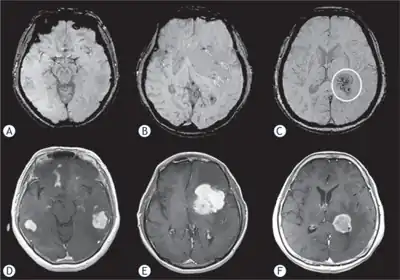

Primary central nervous system lymphoma a) Grade 1: multifocal tumors show no intratumoral susceptibility signal b) Grade 2: shows punctate low-intensity signals arrows c) Grade 3: low-intensity signals circle d,e,f) shows primary central nervous system lymphomas with intense enhancement -

MRI or contrast enhanced CT classically shows multiple ring-enhancing lesions in the deep white matter. The major differential diagnosis (based on imaging) is cerebral toxoplasmosis, which is also prevalent in AIDS patients and also presents with a ring-enhanced lesion, although toxoplasmosis generally presents with more lesions and the contrast enhancement is typically more pronounced. Imaging techniques cannot distinguish the two conditions with certainty, and cannot exclude other diagnoses. Thus, patients undergo a brain biopsy or vitreous biopsy, if there is intraocular involvement.[11]